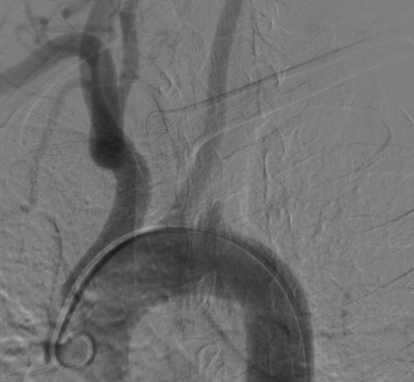

- Sténose sévère ou occlusion de l’artère sous-clavière proximale

- Flux rétrograde dans l’artère vertébrale ipsilatérale

- Phénomène du vol sous clavier: si il y a juste la dérivation de flux

- Syndrome du vol sous-clavier: si il y a des symptomes ischémiques cérébrales associées